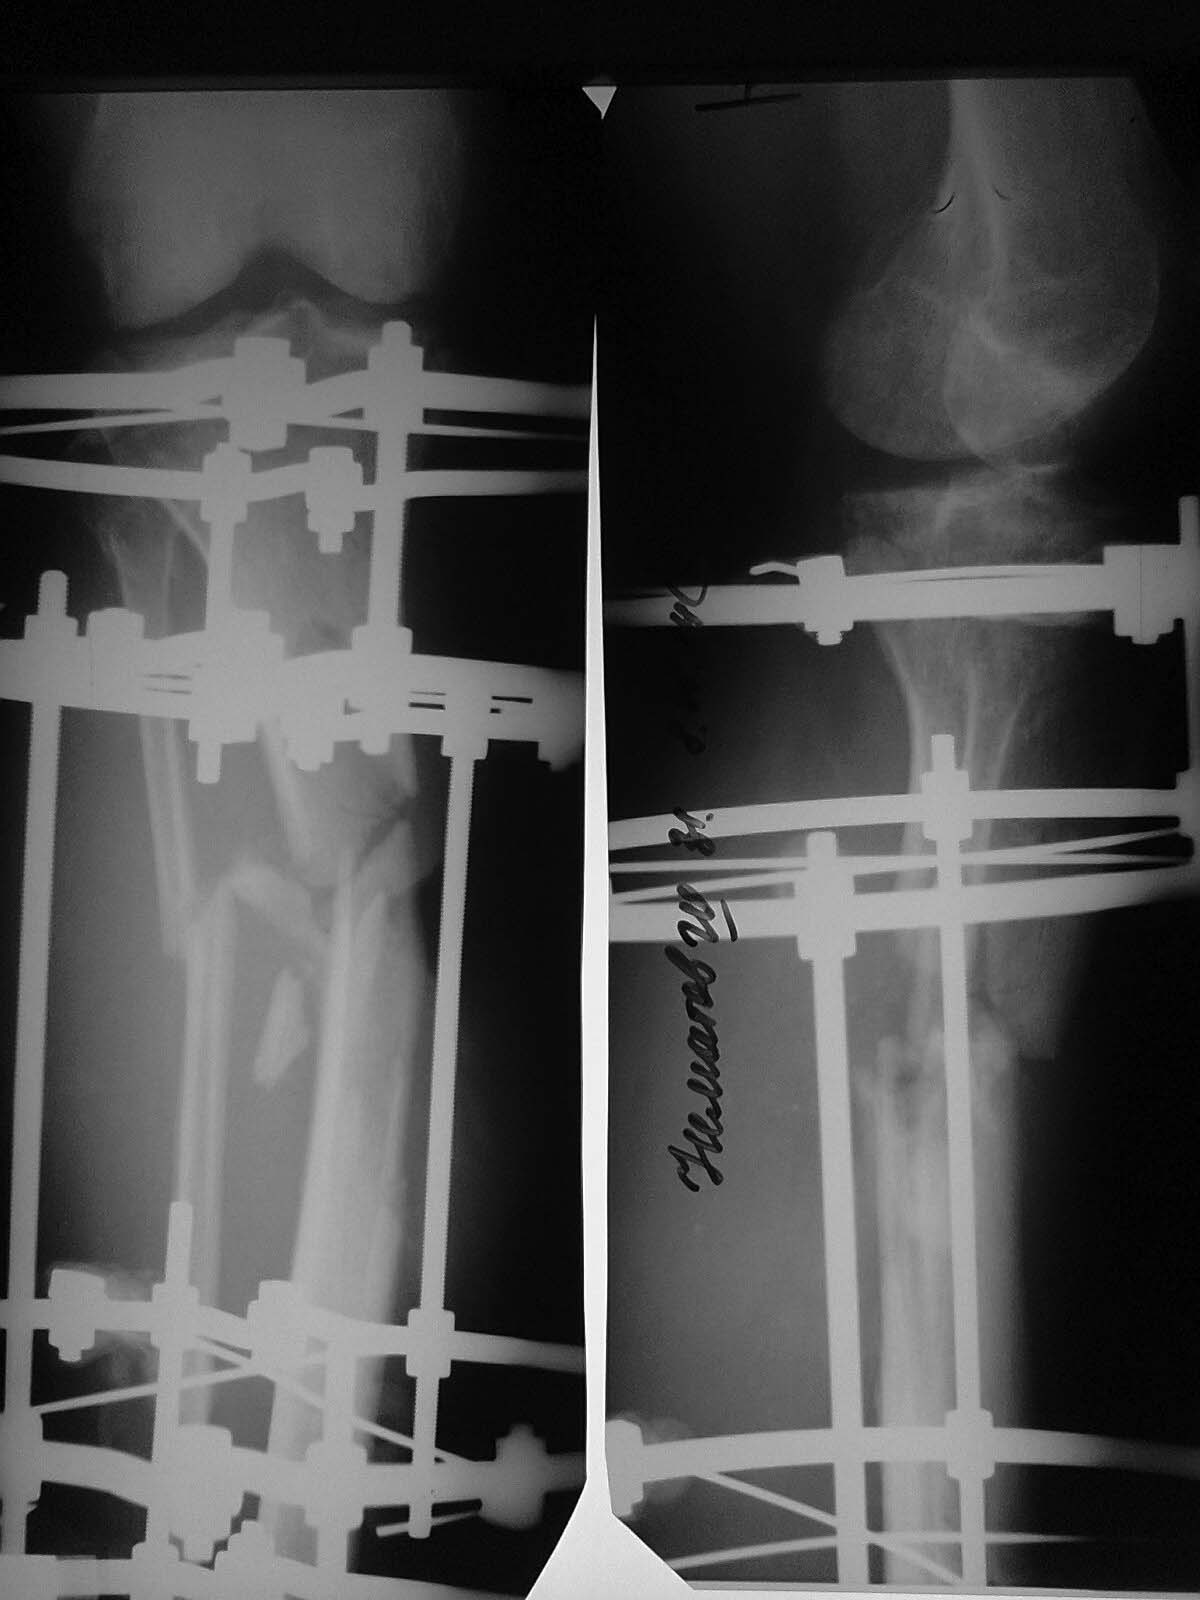

Пациент, 33 г. Травма в мае 2014 года в результате ДТП (сбит машиной).

Оперирован в институте (или центре) травматологии и ортопедии одной из

среднеазиатских республик (уроженец этой республики).

Обратился к нам в августе, по поводу наличия гнойной раны внутренней

поверхности голени с обильным отделяемым. (Рентгенограммы- фото 1).